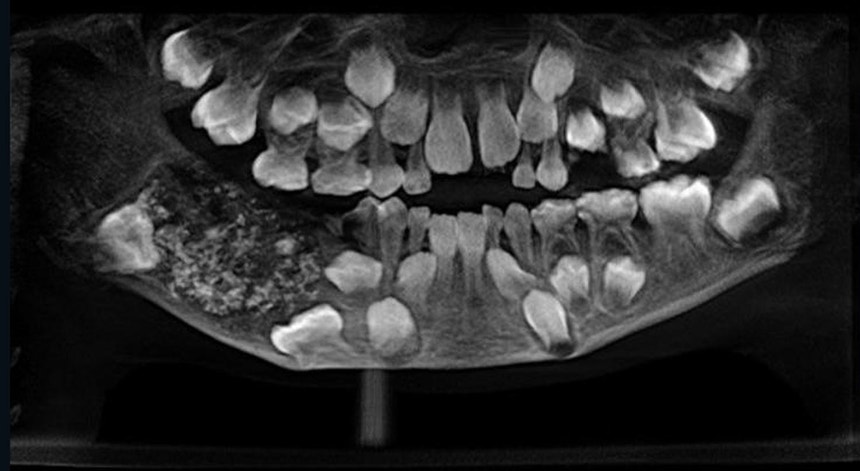

Um menino indiano de sete anos deu entrada num hospital na cidade de Chennai, sul da Índia, com dores fortes no maxilar. Após uma radiografia, os médicos descobriram que a criança tinha 526 dentes a crescer na boca.

A chefe da especialidade de Patologia Oral e Maxilofacial do hospital, Prathiba Ramani confirmou à CNN que quando foi realizada a radiografia os médicos depararam com uma “cavidade embutida no maxilar inferior cheio de dentes anormais”.

“Um total de 526 dentes com tamanhos variáveis entre 0,1 milímetros e 15 milímetros. Mesmo o mais pequeno tinha coroa, raiz e esmalte”, acrescentou.

A criança sofria de uma condição muito rara chamada odontama composto, que poderá ter sido causada por fatores ambientais, como radiação, ou devido à genética.